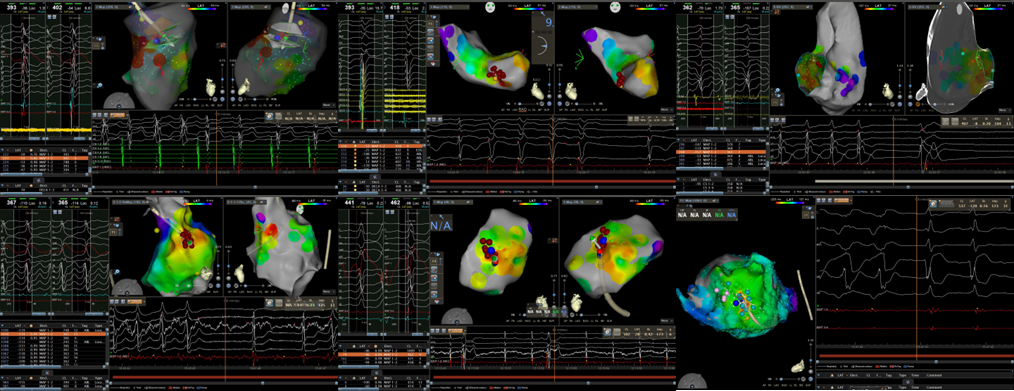

近2周,相继6例无休止室速病例经过药物及电复律治疗无效或治疗期间发生心脏停搏。黑料网心血管内一科起搏电生理团队在面临急诊手术高风险及高不确定因素情况下,应用急诊射频消融方式顺利终止上述患者无休止室速,改善患者血流动力学及心脏功能。

传统认知中,射频消融术只能择期进行,并且仅适用于血流动力学稳定的患者。目前,在成熟完备的标测技术和手段加持下,对血流动力学不稳定的无休止室速行急诊射频消融术能转服窦律,为后续原发疾病诊治或ICD(体内除颤器)植入争取机会。